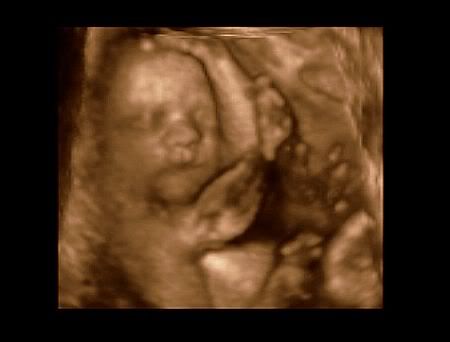

Here are some of Jack's pics.

& even though they did look like him, they didnt look quite as much like him as I expected.

Here are a few of the pics of Caden......I don't have the ones of Conner on this computer.